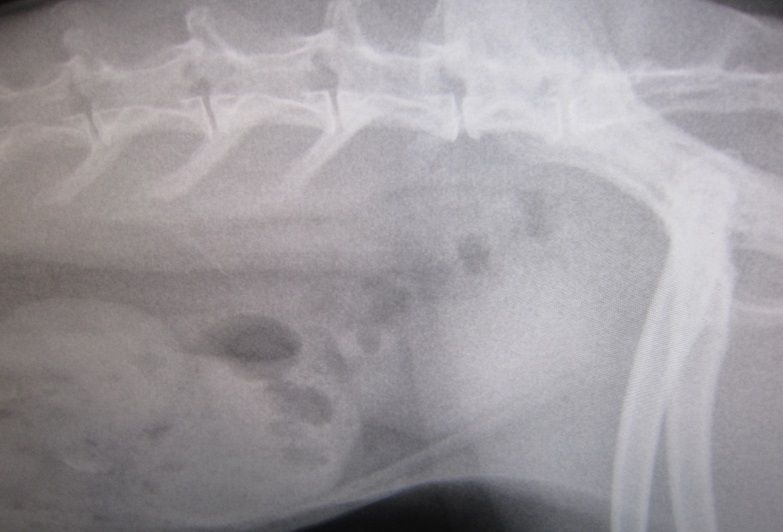

昨夜からの流れを話しし、診察、レントゲン

脂肪、すご過ぎやん…( ̄ェ ̄;)

前回との比較…

前回… とは、最初、あんまりにも食べない食べないで、きちんと痩せた状態、だったので余計かもですが、それでもマズい…

ずっとペレットは朝晩5gずつ。…だのに、増える体重、結果こんな…

ひとまず、カロリー低いペレットに変更はしましたが、

運動も、もっと心がけぇ、牧草ペレットは緑の方に変えようとか

できる範囲でいろいろやっていきつつ、経過見て行きましょう、と。

(内臓脂肪が多いって話で病気とかそんなんではありません)